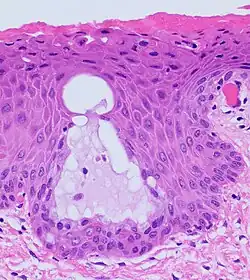

The endocervical mucosa is about 3 mm (0.12 in) thick and lined with a single layer of columnar mucous cells. It contains numerous tubular mucous glands, which empty viscous alkaline mucus into the lumen.[4] In contrast, the ectocervix is covered with nonkeratinized stratified squamous epithelium,[4] which resembles the squamous epithelium lining the vagina.[17]: 41 The junction between these two types of epithelia is called the squamocolumnar junction.[17]: 408–11 Underlying both types of epithelium is a tough layer of collagen.[18] The mucosa of the endocervix is not shed during menstruation. The cervix has more fibrous tissue, including collagen and elastin, than the rest of the uterus.[4]

The squamocolumnar junction of the cervix, with abrupt transition: The ectocervix, with its stratified squamous epithelium, is visible on the left. Simple columnar epithelium, typical of the endocervix, is visible on the right. A layer of connective tissue is visible under both types of epithelium. -

Nabothian cysts (or Nabothian follicles) form in the transformation zone where the lining of metaplastic epithelium has replaced mucous epithelium and caused a strangulation of the outlet of some of the mucous glands.[17]: 410–411 A buildup of mucus in the glands forms Nabothian cysts, usually less than about 5 mm (0.20 in) in diameter,[4] which are considered physiological rather than pathological.[17]: 411 Both gland openings and Nabothian cysts are helpful to identify the transformation zone.[15]: 106